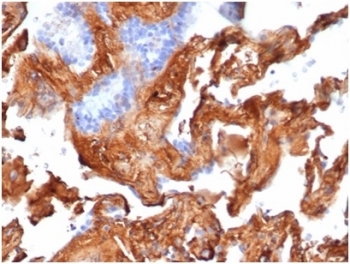

Fibronectin 1 Antibody Human Lung IHC. Immunohistochemistry analysis of FFPE human lung tissue stained with clone FN1/3569. Extracellular and pericellular HRP-DAB brown staining is observed within stromal connective tissue and alveolar-associated matrix structures, consistent with expression of Fibronectin 1 / FN1, a major extracellular matrix glycoprotein involved in tissue remodeling, cellular adhesion, and stromal organization pathways. Surrounding epithelial cells show comparatively lower staining intensity. HIER: boil tissue sections in pH 9 10mM Tris with 1mM EDTA for 20 min and allow to cool before testing.